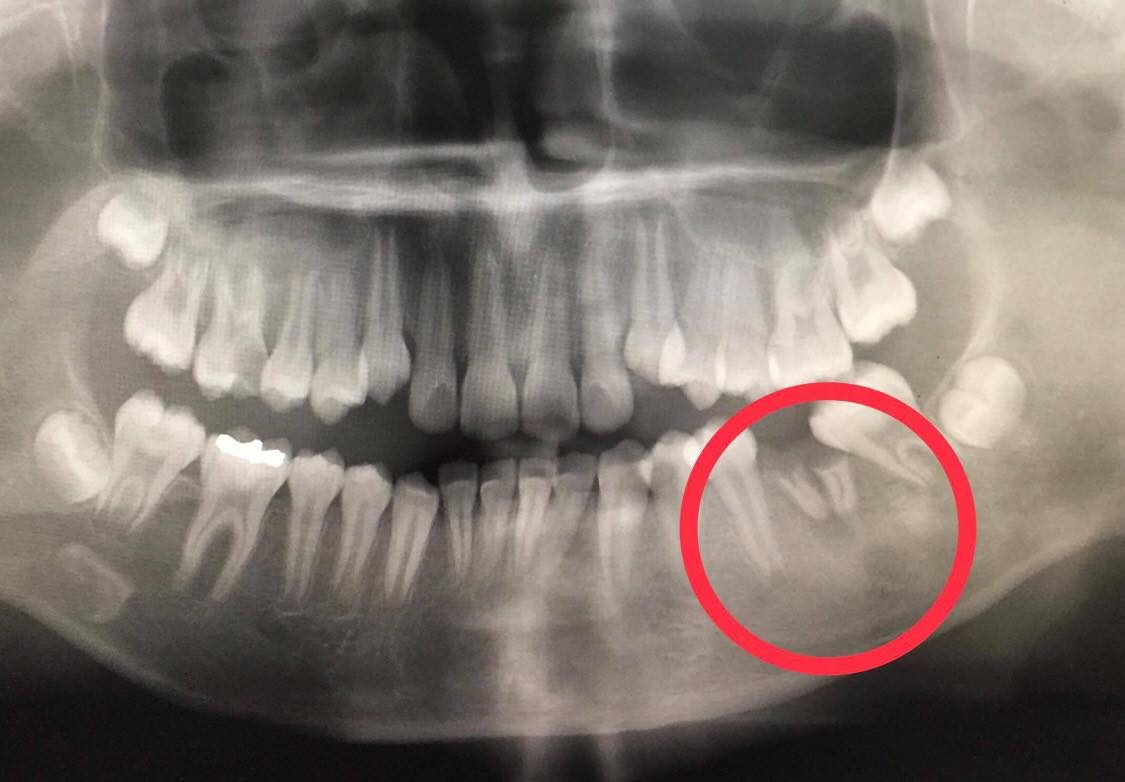

เมื่อเอ็กซเรย์ทั้งปาก พบฟันกรามล่างซี่ที่ 36 ผุจนเหลือแต่ตอฝังอยู่ในเหงือก ทันตแพทย์จึงทำการถอนรากฟันให้คนไข้ ล้างแผลใต้คางที่เป็นรูเปิดของหนอง หลังจากนั้นแผลก็หายสนิท คนไข้ไม่ต้องทนทุกข์ทรมานต่อไป เรื่องนี้เรียกได้ว่าเป็นปัญหาเส้นผมบังภูเขาจริงๆ